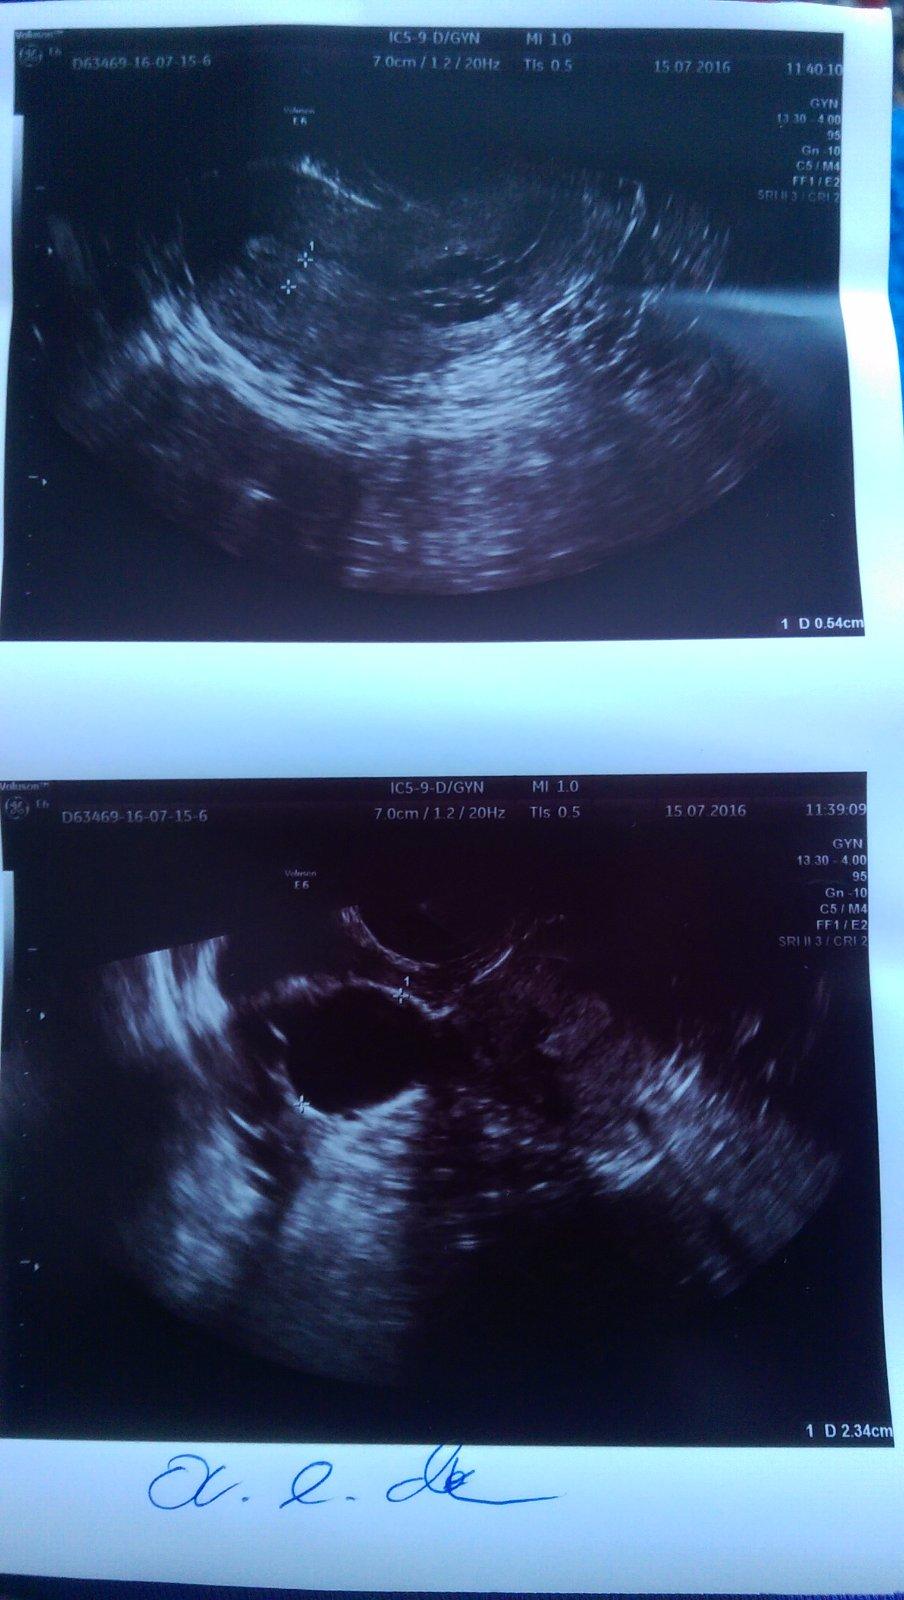

MS mi začala na 34 DC to bolo 27.06.2016...teraz v utorok 16 DC pichli 19:05 h. Pregnyl 10 tisíc jednotiek a v piatok 19 DC o 11:30 h. kontrolné sono a fólikul mal 23 mm na pravom vaječníku...v sobotu som cítila pobolievanie podbruška, aj pravý vaječník...som zvedavá na výsledok 😉 od 12.07.2016 mi zvýšili Euthyrox na 75 mg